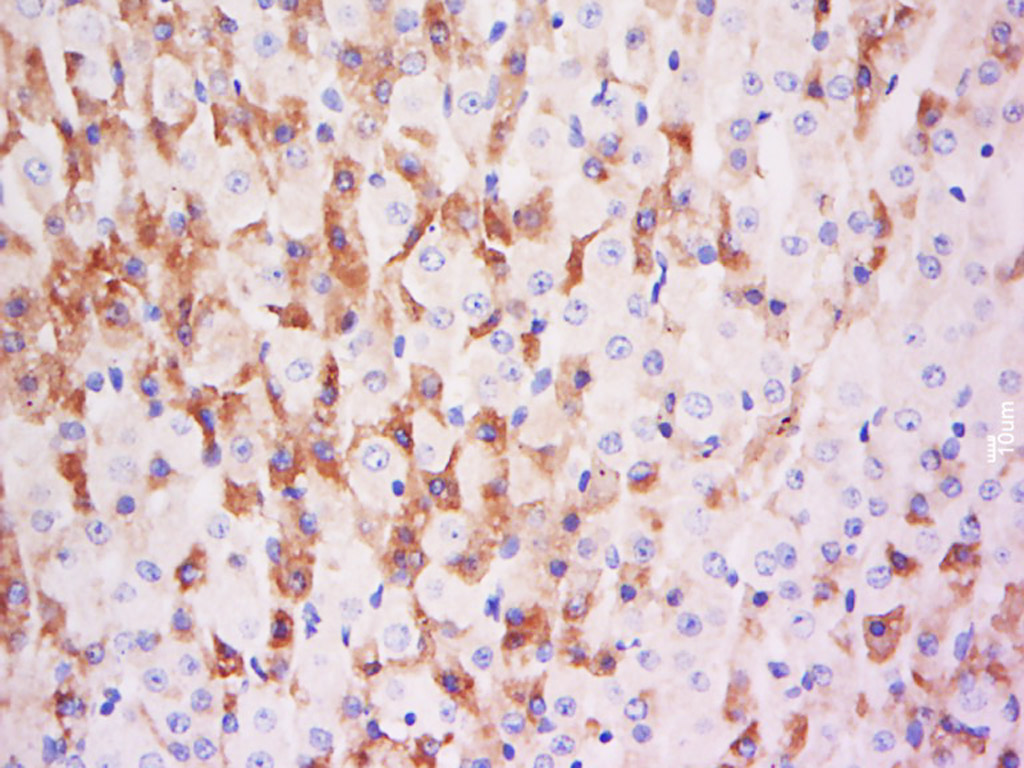

Tissue/cell: rat brain tissue; 4% Paraformaldehyde-fixed and paraffin-embedded;

Antigen retrieval: citrate buffer ( 0.01M, pH 6.0 ), Boiling bathing for 15min; Block endogenous peroxidase by 3% Hydrogen peroxide for 30min; Blocking buffer (normal goat serum,C-0005) at 37℃ for 20 min;

Incubation: Anti-ADM/AM/Adrenomedullin Polyclonal Antibody, Unconjugated(bs-0007R) 1:200, overnight at 4°C, followed by conjugation to the secondary antibody(SP-0023) and DAB(C-0010) staining